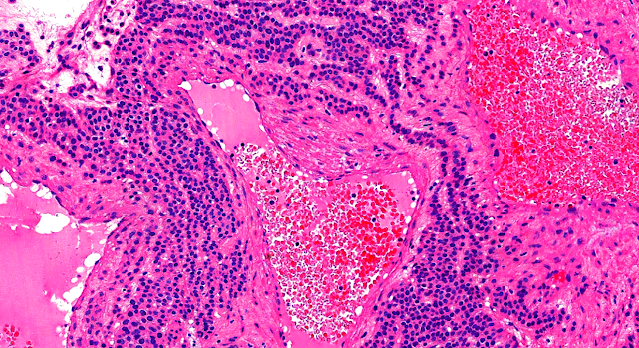

Dermatopathology Case 219 Get link Facebook X Pinterest Email Other Apps May 23, 2022 A 35 year old man with a nodule on the left middle finger. Answer Get link Facebook X Pinterest Email Other Apps Comments